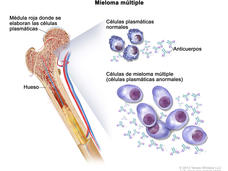

La FDA aprueba una indicación más amplia para carfilzomib en pacientes con mieloma múltiple

La FDA ha aprobado carfilzomib en combinación con otros fármacos anticancerosos para el tratamiento de pacientes con recidiva de mieloma múltiple.